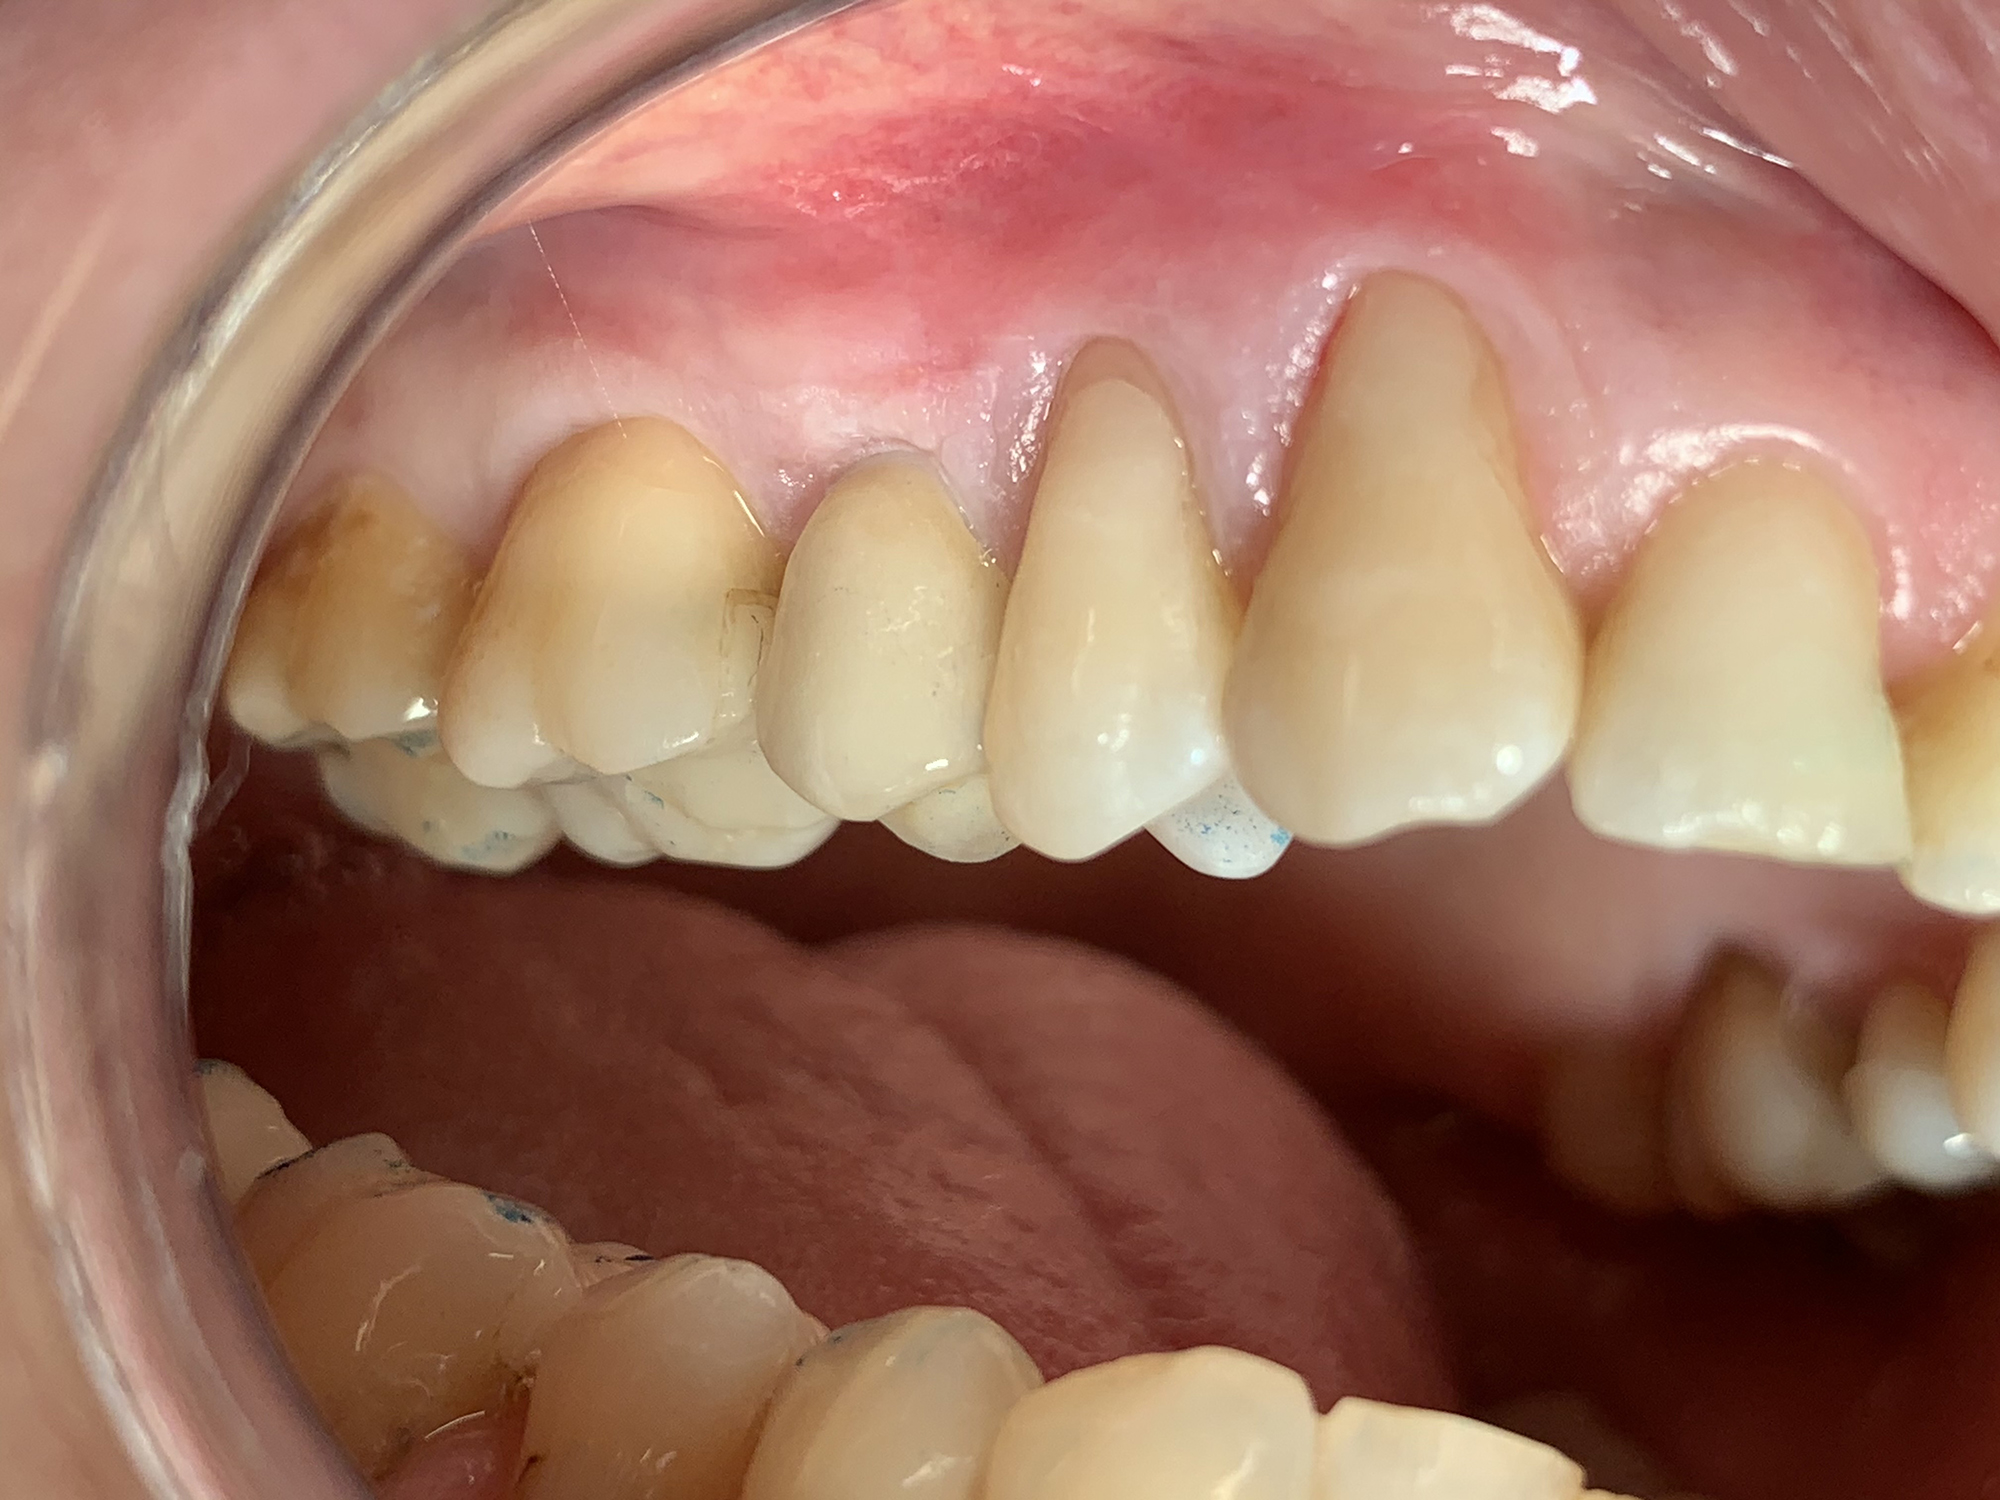

Keramikimplantate

Wir setzen auf hochwertige Keramikimplantate von Swiss Dental Solutions. Diese sind metallfrei, ästhetisch, verträglich und lassen sich oft in nur einer Sitzung einsetzen – für ein natürlich schönes Lächeln.

Überzeugende Vorteile von SDS Keramik-Implantaten

• Die helle Farbe im Vergleich zu den schwarzgrauen Titanimplantaten garantiert ein natürliches Lächeln und eine herausragende Ästhetik